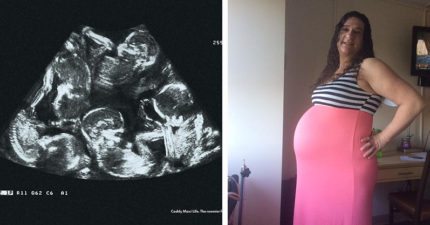

辛苦媽媽努力10年流產4次,老天不忍決定把驚喜「一次還給她」!